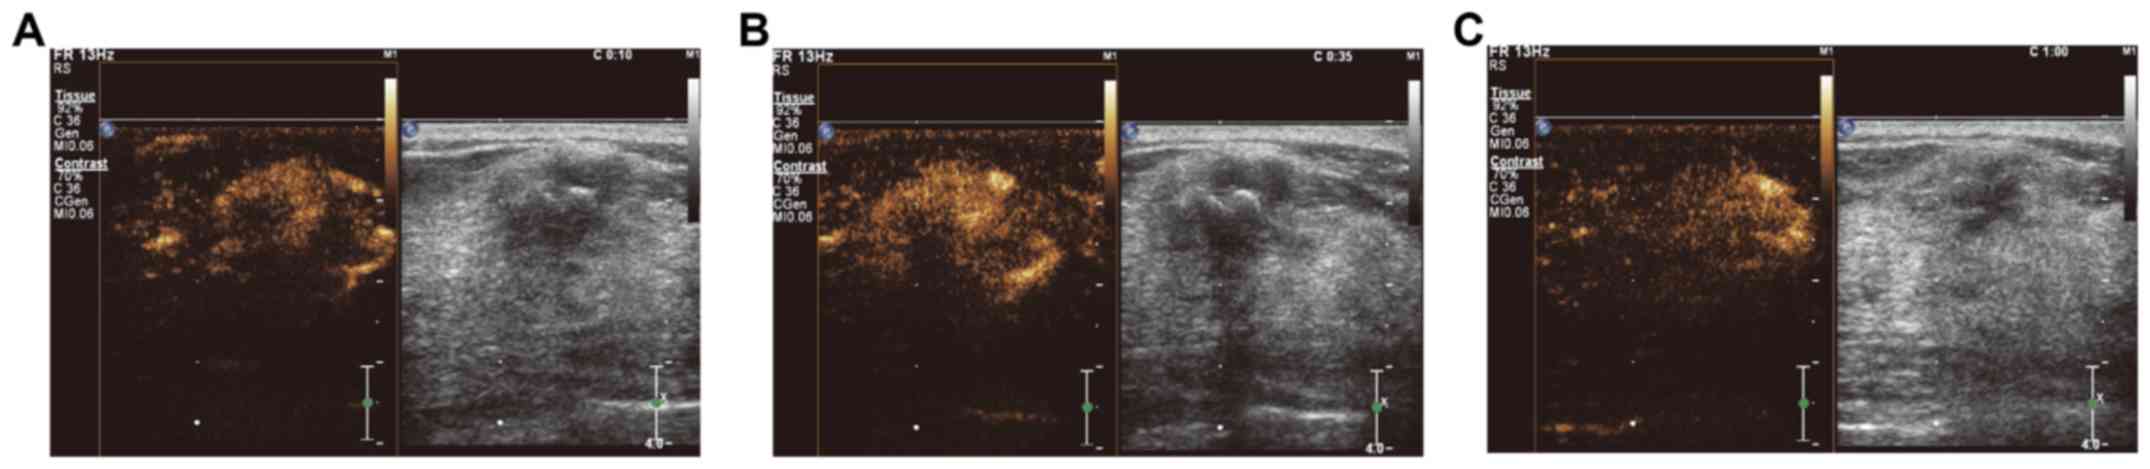

Clinical value and application of contrast-enhanced ultrasound in the differential diagnosis of malignant and benign breast lesions

The aim of the present study was to assess the performance of contrast-enhanced ultrasound in distinguishing between malignant and benign breast lesions and the diagnostic value of its clinical application. A total of 52 cases with malignant breast tumors and 73 cases with benign breast lesions were included in the study. Time-intensity curves (TICs) for contrast-enhanced ultrasound were recorded, and the perfusion parameters were obtained and analyzed. Typical features of malignant breast tumors included irregular shape and vascular morphology, uneven contrast agent distribution, filling defects and contrast agent retention, ‘fast-out’ wash-out mode, unclear boundaries and uneven internal echo. Benign lesions were characterized by ‘slow-out’ or synchronous wash-out mode. Regarding perfusion, the starting time of the perfusion of the Sone-Vue microbubble contrast (always 20-30 sec) and time to peak (TTP) were significantly earlier for the malignant lesions, while the wash-out time was later. A significantly greater peak intensity, rising slope and area under the TIC were observed for the malignant breast lesions. All of the malignant breast lesions exhibited an enlarged focus scope on ultrasound, while no obvious focus scope enhancement was observed for benign breast lesions. Furthermore, the TICs of 88.4% of malignant breast lesions were of the fast-rising and slow-declining type, while the TICs of 75.3 and 17.8% of the benign breast lesions were of the slow-rising and fast-declining, and fast-rising and fast-declining type, respectively. Receiver operating characteristics analysis indicated that the TTP, wash-out time and rising slope might contribute to the differential diagnosis between malignant and benign breast lesions. In conclusion, TIC parameters of contrast-enhanced ultrasound have promising clinical value in differentiating between malignant and benign breast lesions. The TTP, wash-out time and rising slope may contribute to the diagnosis of patients with breast lesions to facilitate timely treatment and prognostication of breast cancer patients.